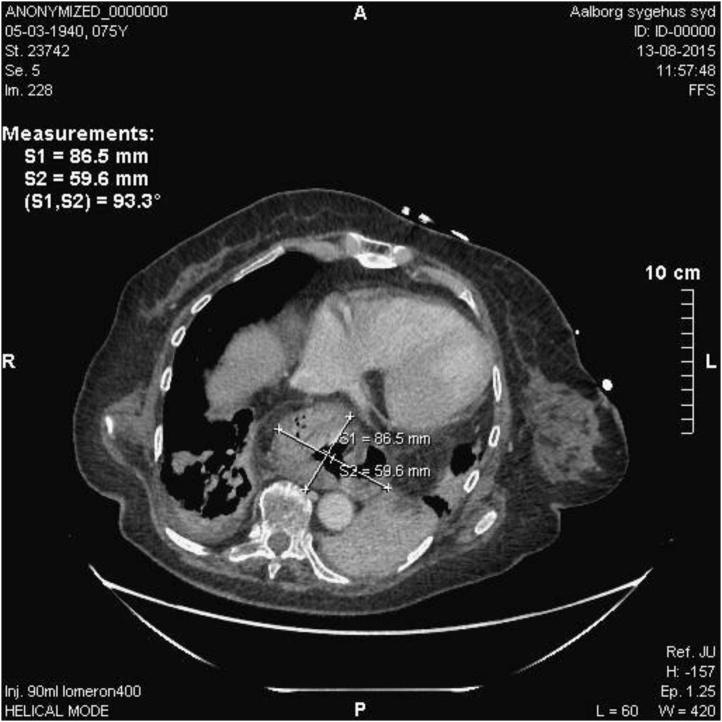

PRESENTATION OF CASE

We present a case of a 75-year-old female who was acutely admitted with stridor. The patient was known to have a paraesophageal hernia monitored using watchful waiting, and dyspnoea. The patient's condition deteriorated, leading to intubation. Diagnostic imaging revealed a paraesophageal hernia pressing onto the trachea as well as appendicitis and ileus. Surgery confirmed perforated appendicitis, peritonitis, and ileus causing high intra-abdominal pressure, resulting in further herniation of the paraesophageal hernia as a cause for acute compromised respiratory function. Appendectomy and gastropexy were performed. The patient was later discharged to rehabilitation.

病例介绍

我们报告一例75岁女性患者,因急性喘鸣入院。已知该患者患有食管旁疝,一直采用观察等待策略进行监测,且有呼吸困难症状。患者病情恶化,最终进行了插管。诊断性影像学检查显示食管旁疝压迫气管,同时伴有阑尾炎和肠梗阻。手术证实为穿孔性阑尾炎、腹膜炎和肠梗阻,导致腹内压升高,致使食管旁疝进一步突出,成为急性呼吸功能受损的原因。进行了阑尾切除术和胃固定术。患者后来出院接受康复治疗。